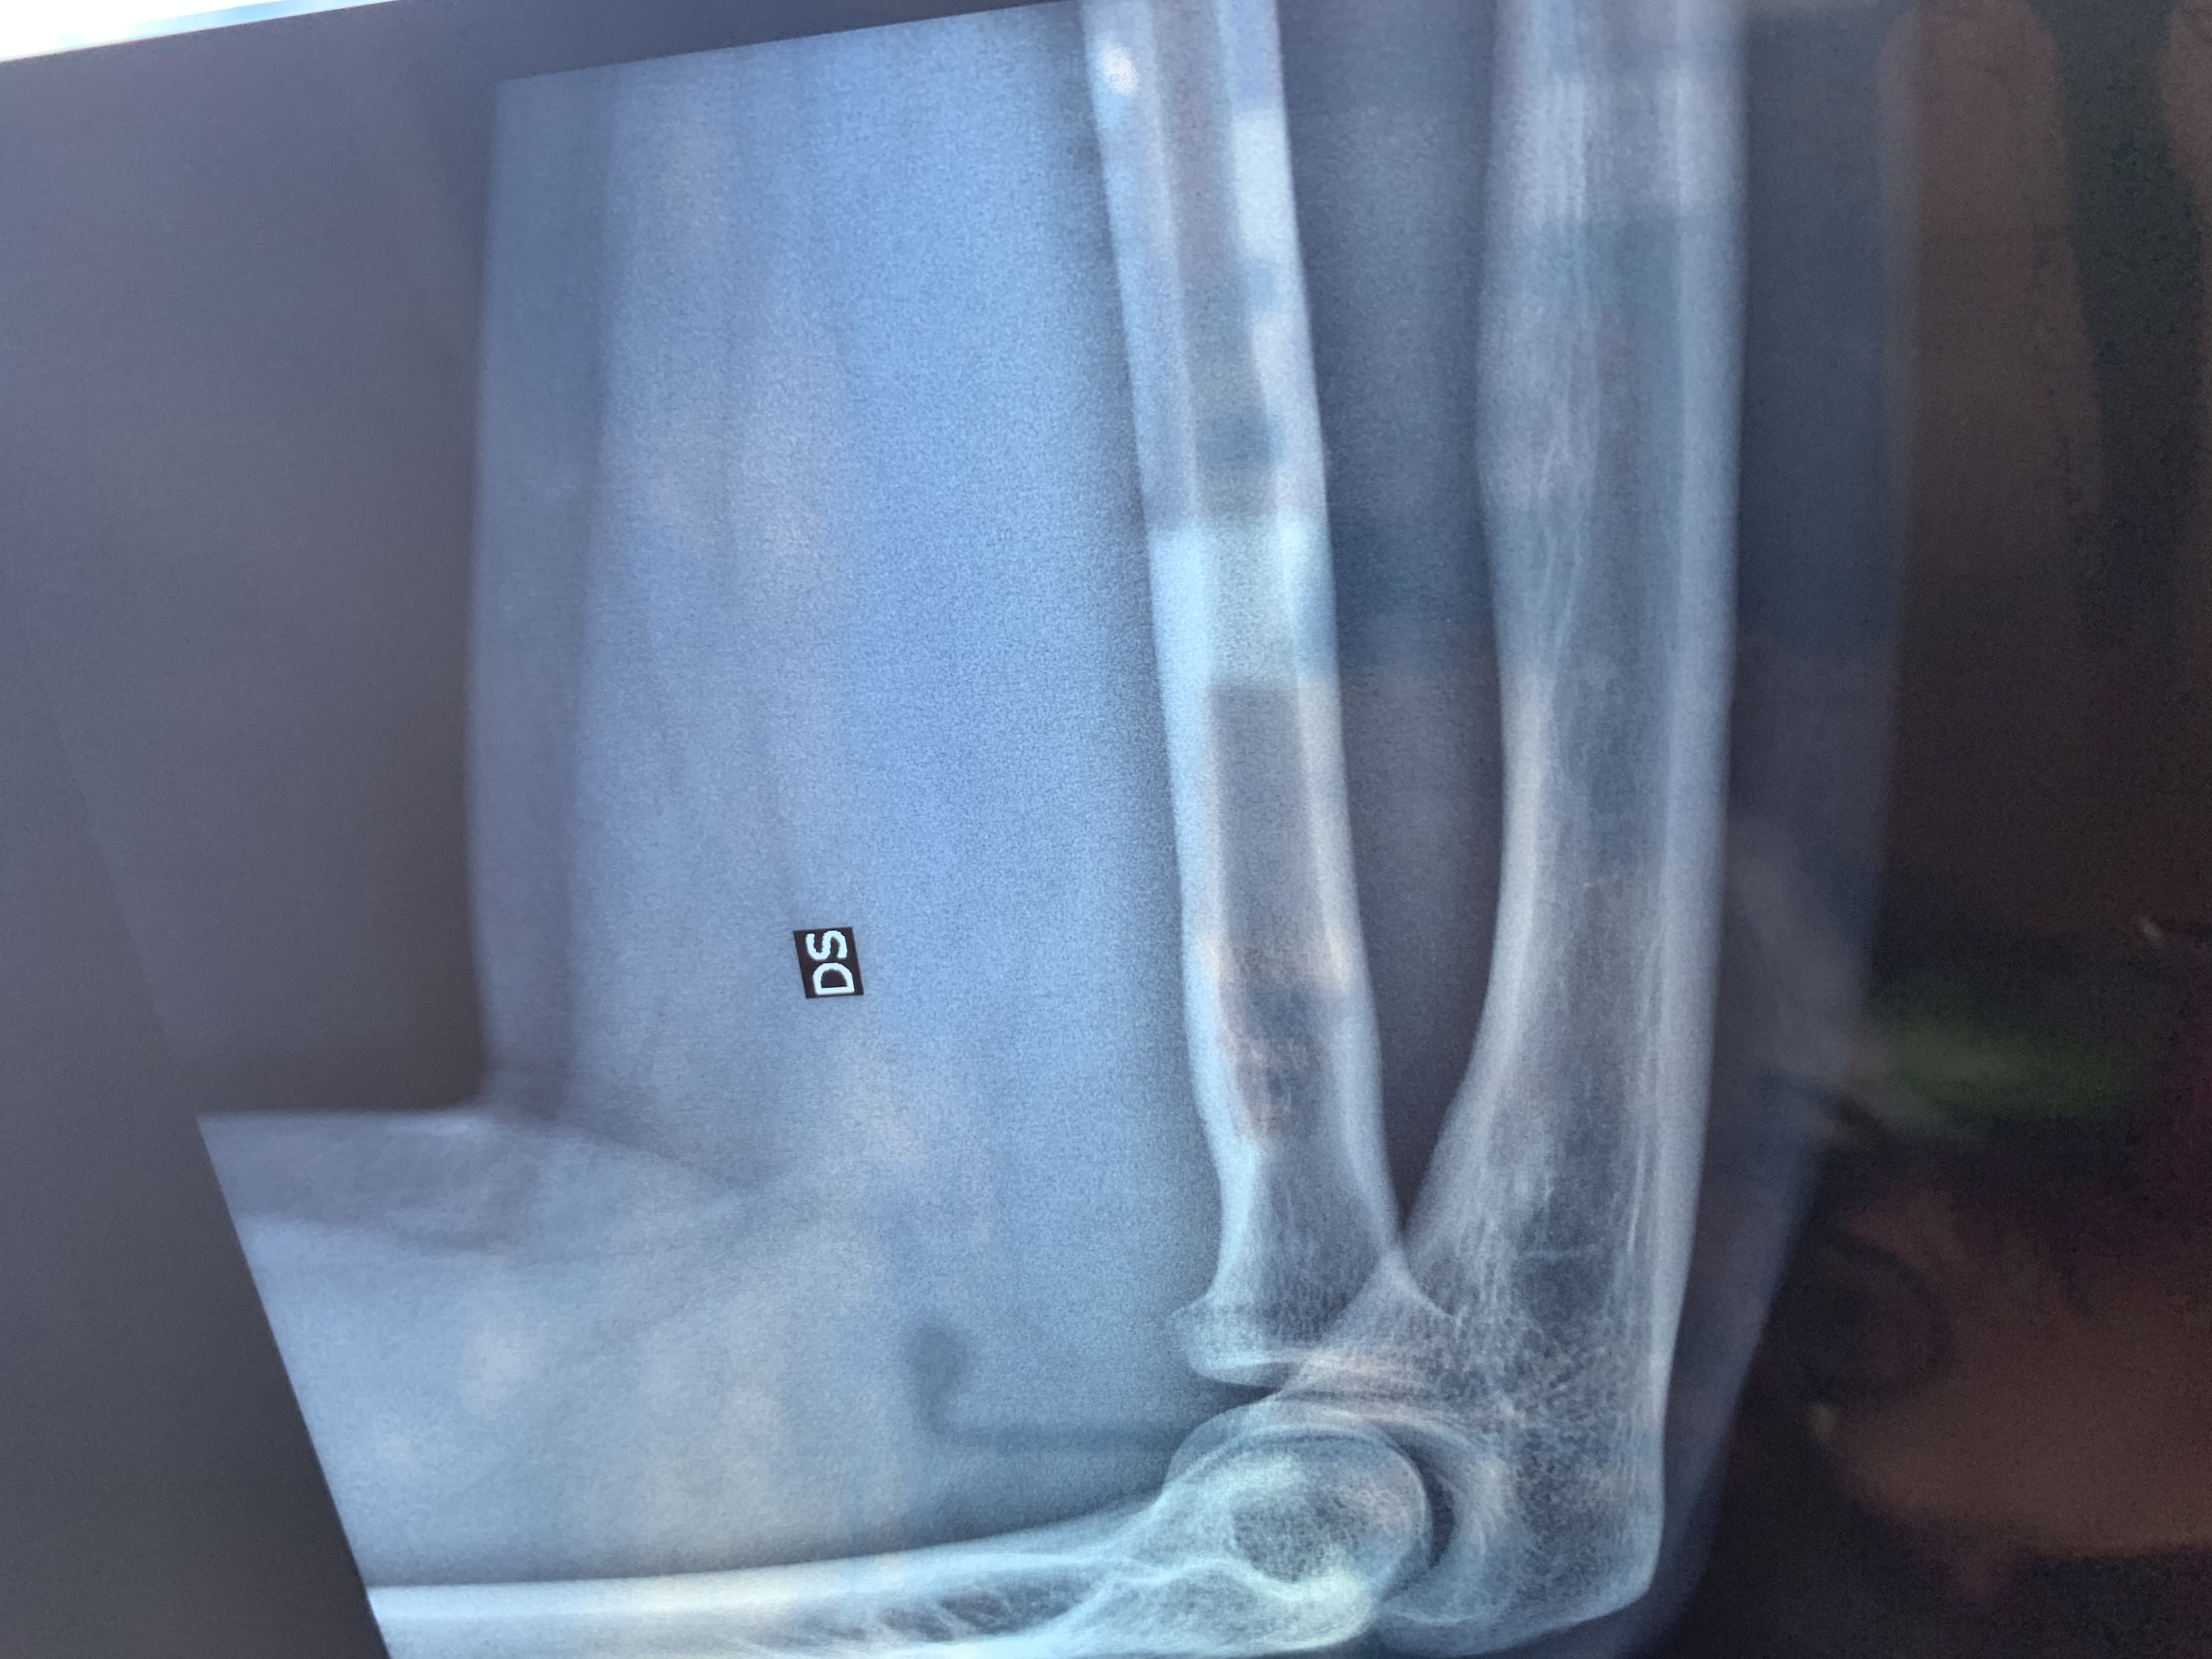

Buonasera, ieri in data 21 maggio mentre giocavo a calcetto tra amici, purtroppo durante un contrasto sono caduto.. il peso del corpo è caduto tutto sul mio braccio destro, ho sentito in un primo impatto un dolore lancinante, però subito dopo ho continuato a giocare a mia insaputa della gravità del problema, ho continuato a giocare per circa 1 ora, senza alcun evidente problema. Tornato a casa applico una pomata antinfiammatoria e una fascia che immobilizza non totalmente il gomito. In mattina mi reco in pronto soccorso,dagli esami rx viene rilevata una frattura composta del capitello radiale dx con componente intra-articolare con seguente visita ortopedica con immediata doccia gessata per 25 giorni . L

Ortopedico mi ha consigliato di ritornare entro una decina di giorni per altro controllo ,la

Mia domanda per voi è c’è la possibilità che mi venga tolto il gesso e applicata una fascia ? Inoltre il mio dubbio consiste nel riprendere la piena mobilità dell articolazione del gomito visto che tra due mesi ho un impegno lavorativo importante. In allegato i referti rx . Grazie attendo buone nuove

Commento file: Prima lastra

C058E174-599E-48A8-B47F-D606BF06CC6D.jpeg